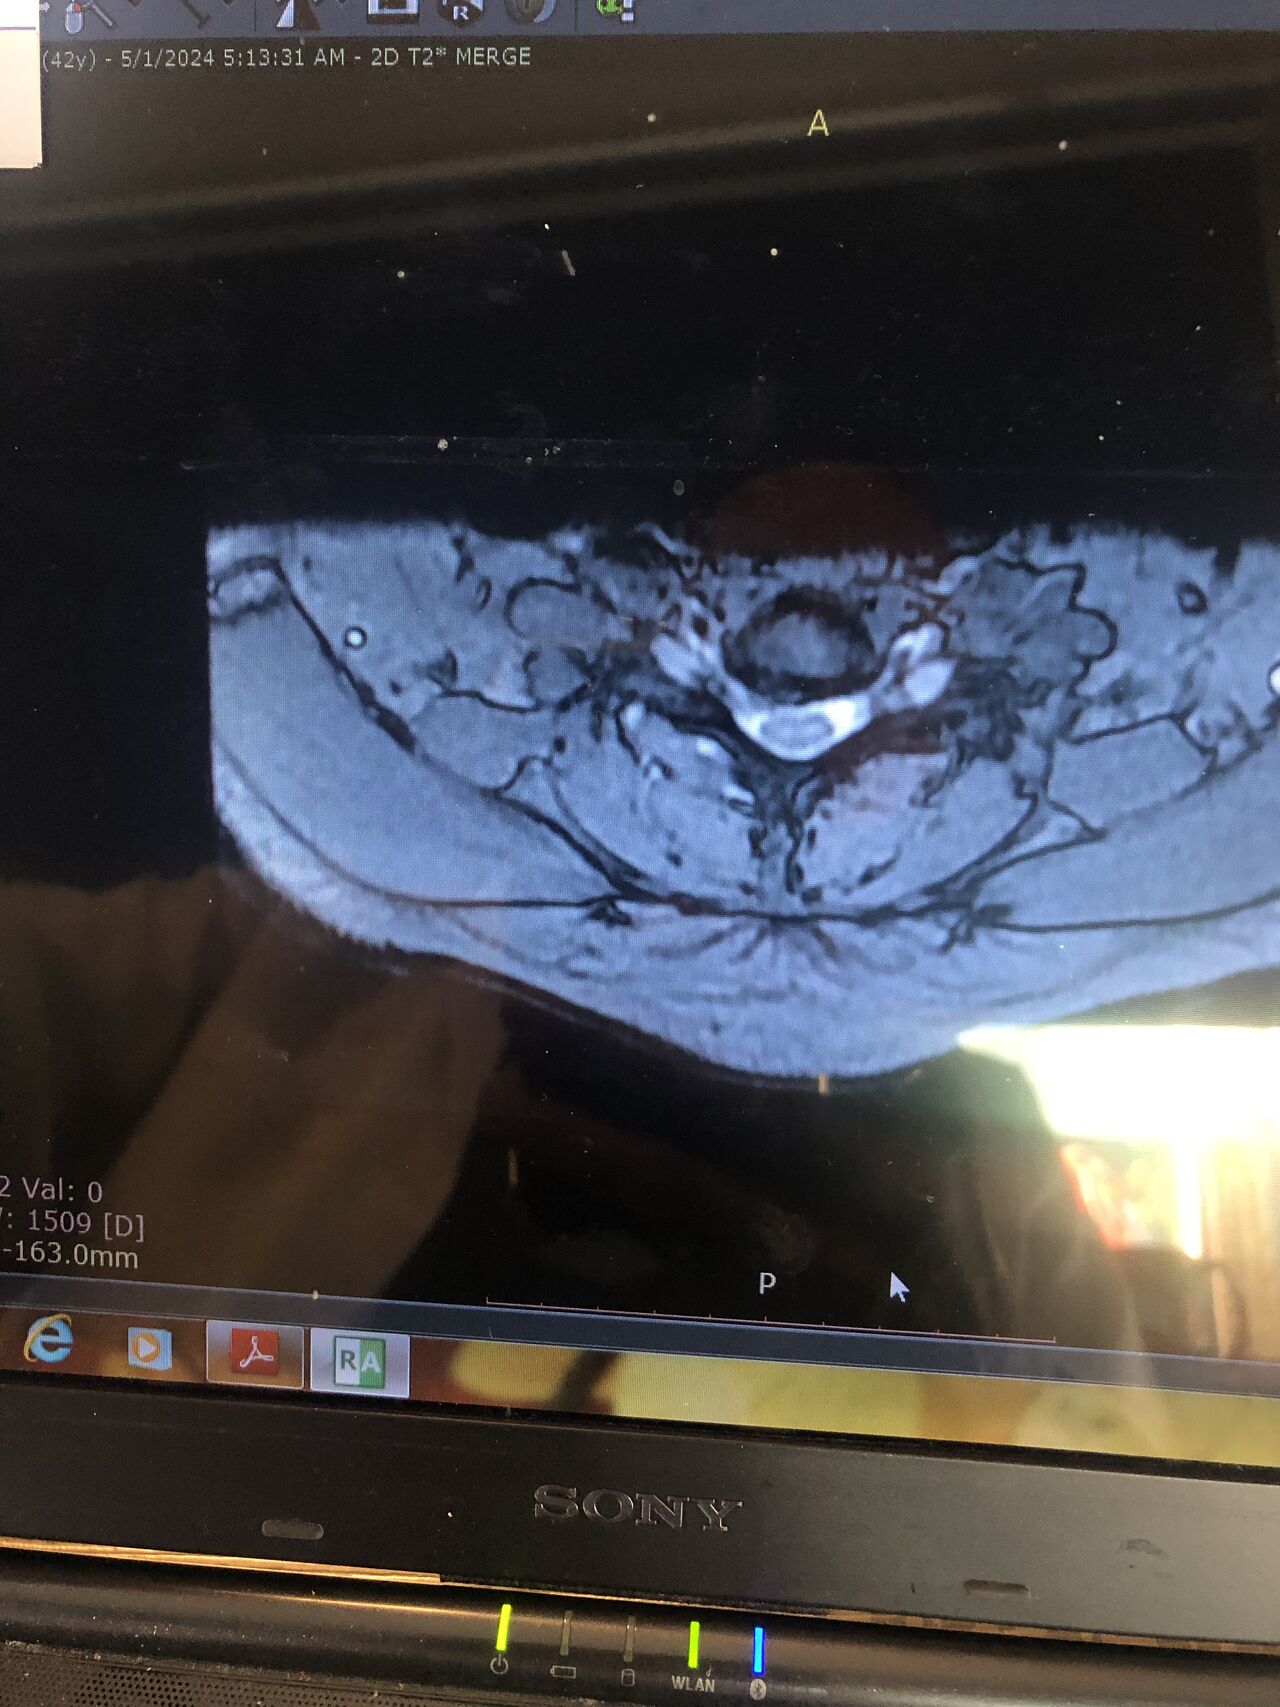

41 years old man presented to my clinic in October 2023 with acute and sever R neck pain with radicular pain to his R upper extremity along C6 dematom since 2 weeks ago. Examination didn’t show any upper motor signs. Was suggested urgent surgery

I ordered EMG/ NCV : showed mild R C6, C7 irritation without any active axonal loss

In his MRI was reported R. para R. IVF Massive extrusion. I decided to control his pain and manage this patient with reevaluation of patient every other session. For 5 sessions i just used acupuncture and laser and IFC and mild adjustments to his R. T3-T7 and mild arthosteem to above and below involved segment. Cervical adjustment considered contraindicated for this patient. From session 6th- 8th i started to use mild/gentle cervical decompression. He used soft cervical collar all the time. His pain decreased by 80 percent

I gave him cervical traction pump to be used 3-5 times per day at home for the next 3 months and i released the patient. He was evaluated every week once for one month and after that every 2 weeks. After 3 month I repeated MRI. Size of the herniated disc was reduced greater than 50 percent. Asked him to do another mri in 6 months

MRIs before and after proper management of this patient: